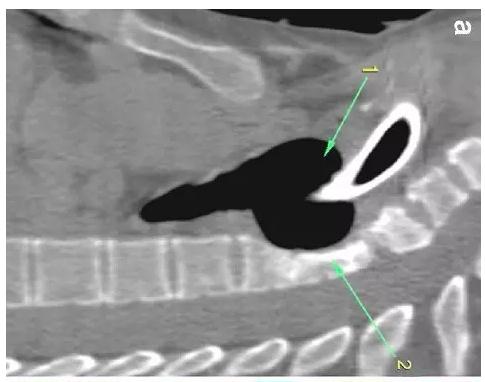

胸部CT顯示氣切套管氣囊周圍氣管擴張,胸1-4椎體前部受到侵蝕(下圖a-c)。

下圖箭頭1為氣切套管氣囊緊貼T1-4椎體水平,造成椎體前部受到侵蝕(箭頭2):